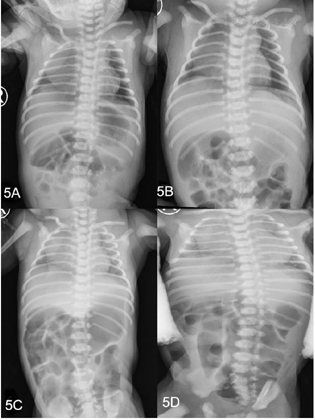

患儿辅助检查提示多系统异常。头颅磁共振成像显示双侧脑室周围结节性异位和大枕大池(图4)。胸部X光显示心影逐渐扩大,同时伴有双肺渗出增多,腹部X光显示肠管扩张,伴发多个气液平面(图5)。超声心动图显示心功能不全、房间隔缺损、动脉导管未闭、二尖瓣发育不良和主动脉扩张。泌尿超声检查发现肾积水。脑干听觉诱发电位显示双耳听通路明显延迟。血液生化检查提示肝酶、心肌酶、B型脑钠肽升高,严重的低钠低氯性碱中毒同时合并低钾血症。新生儿期甲状腺功能检测显示总T4(total T4, TT4)93.40 nmoL/L↓(正常:105.5~208.5 nmoL/L),促甲状腺素(thyroid stimulating hormone,TSH)18.58 uIU/ml↑(正常:0.66~6.29 uIU/ml)。随访过程中发现患儿出现严重的甲状腺功能减退,TT4显著降低(TT4 29.00 nmoL/L),TSH显著升高(>150 uIU/ml)。甲状腺超声显示甲状腺大小正常。